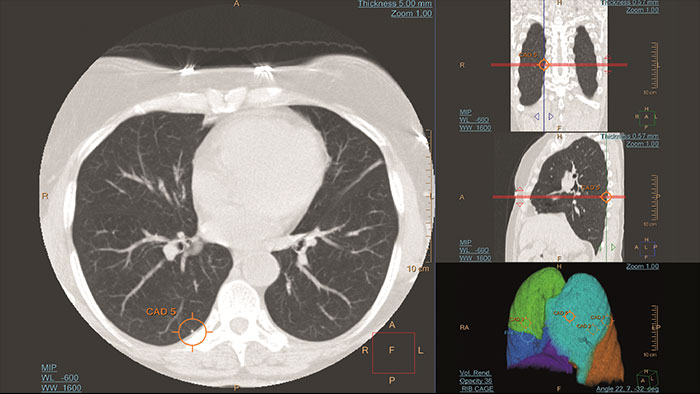

- Lung Nodule Assessment (LNA)

CT Lung Nodule Assessment (LNA)

Assessing lung nodules over time

Enables review and analysis of thoracic CT images, providing segmentation, quantification and characterization of physician-indicated lung nodules. The application can be used in both diagnostic and screening evaluations, supporting Low Dose CT Lung Cancer Screening*

Benefits

- Automatic lung and lobes segmentation and one click 2D and 3D nodule segmentation.

- Supports LungRADS categorization, Fleischner Society guidelines for incidental findings as well as a Risk Calculator tool**.

- Pre-filled data including characteristics for each nodule in configurable presets are provided automatically by the application.

- Lung and nodule segmentations can be shared as RT Structures.

CT Lung Nodule CAD*

Automated computer aid for lung nodule detection

Artificial second reader to support the detection of lesions or nodules which may have been missed. It offers an automated process that identifies and marks regions of interest based on image features associated with lung nodules.

It is intended for use as a second reader after an initial interpretation of the diagnostic image has been performed.

Benefits

- Volumetric segmentation detects nodules based on size, shape, density, and anatomical context.

- One-click display of the findings.